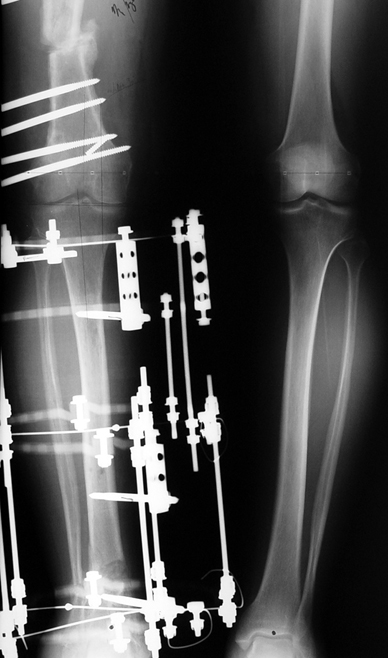

Vaka 2